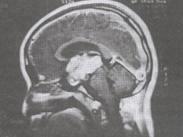

小兒鞍上生殖細胞瘤癥狀

• 小兒鞍上生殖細胞瘤